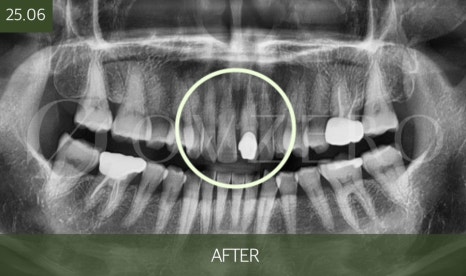

신경치료 시기를 놓치면

치아 뿌리 쪽 염증이 커지면서

치아를 살릴 수 없게 되는

상황으로 이어질 수 있습니다.

이 경우에는

신경치료 → 크라운으로 끝날 치료가

발치 → 임플란트나 브릿지로 바뀔 수 있습니다.